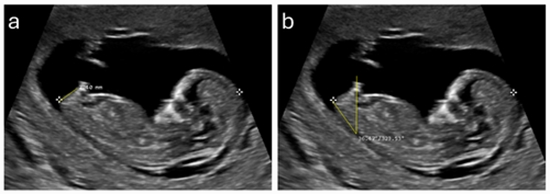

The diagnostic value of the sacrovesical distance in ultrasound to predict the gender of the fetus in the second trimester of pregnancy